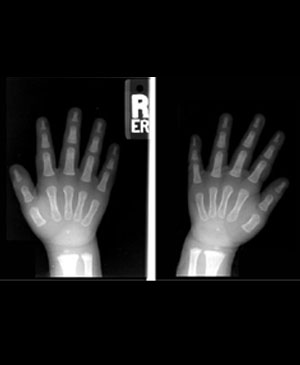

구루병 (Rickets)

X-선 소견

골음영의 감약

골량의 섬세, 거칠다

골간단의 배상변형

예비 석회화증의 소실, 쇄모상 소견

성장판 폭의 증대

골간부의 이중윤곽

Rapid growing end에 변화가 강하다